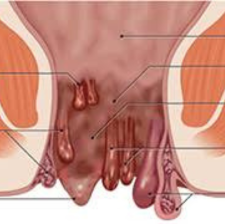

Piles

Hemorrhoids (HEM-uh-roids), also called piles, are swollen veins in the anus and lower rectum. Hemorrhoids are similar to varicose veins. Hemorrhoids can develop inside the rectum, called internal hemorrhoids. They also can develop under the skin ar